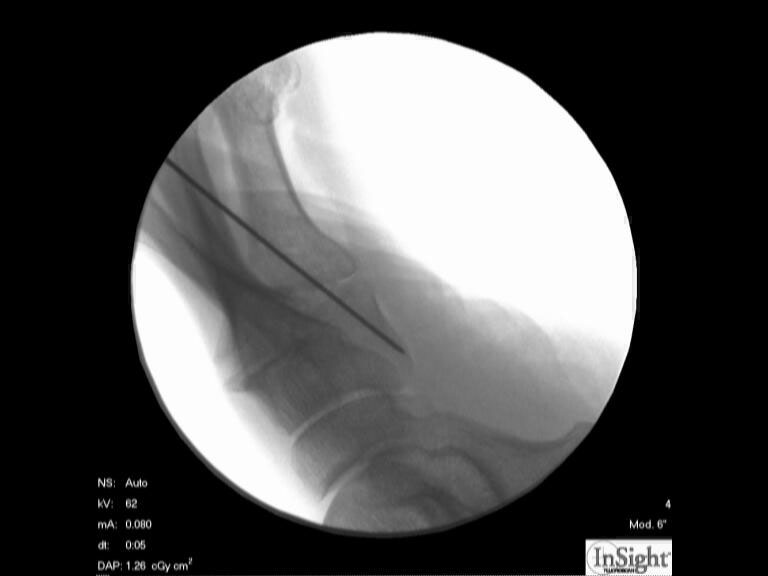

Röntgenaufnahme des Fußes (unter Belastung) in dorsoplantarem, seitlichen und schrägem Strahlengang (Abb. 1a-c).

Zur Vollansicht bitte die Bilder anklicken.

Abbildung 1a

Abbildung 1b

Abbildung 1c